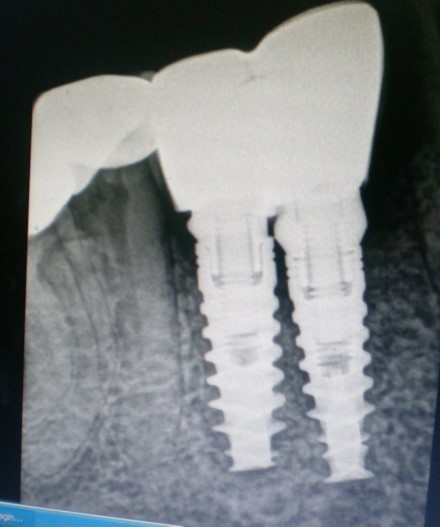

The separator spray (Detax, Germany) was applied around the impression copings (Figure 7) before the application of artificial gingiva (Esthetic mask, Detax, Germany) for easy separation of artificial gingiva from impression material as both are silicones. The artificial gingiva was applied around impression copings and the impression was poured with type IV gypsum product ((Kalstone; Kalabhai Karson Pvt. Ltd. India) to obtain the master cast (Figure 8), which, with a soft tissue gingival mask, will allow the restorative dentist and technician to choose the ideal abutment and technique for the case. Further , the accuracy of the impression was verified with verification jig. the verification jig should fit passively on the cast as well as in patient mouth. After verification jig trial, the prosthesis (two joined PFM crowns, Figure 9 and Figure 10) was fabricated over two modified castable UCLA abutments (PLA-R straight plastic abutments, AlphaBio, Israel). The final prosthesis was cemented with chemical cure resin cement.

Figure 9.Radiograph verifying the fit of the abutment

Radiograph verifying the fit of the abutment